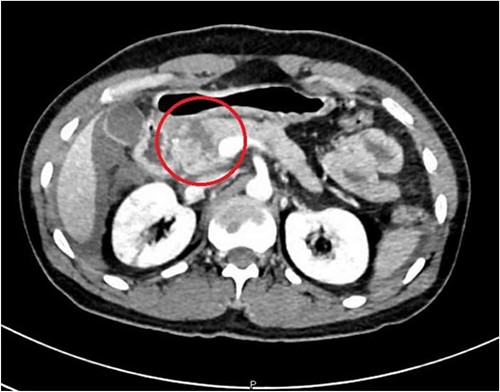

A 36-year-old male manual laborer was assaulted by his roommates (kicked in the abdomen multiple times) and was intoxicated with alcohol. He was writhing in pain, hemodynamically stable with a guarding abdomen. Initial laboratory results showed high serum amylase level 485 U/L, high serum lipase 1200 U/L and elevated liver enzymes. A computed tomography (CT) scan revealed an enlarged bulky head of the pancreas with complete transection of the pancreatic neck (Figs 1–2). In addition, he had a small contusion of the liver and free fluid in the abdomen.

CT abdomen—coronal section, showing transection of the pancreas (circle).